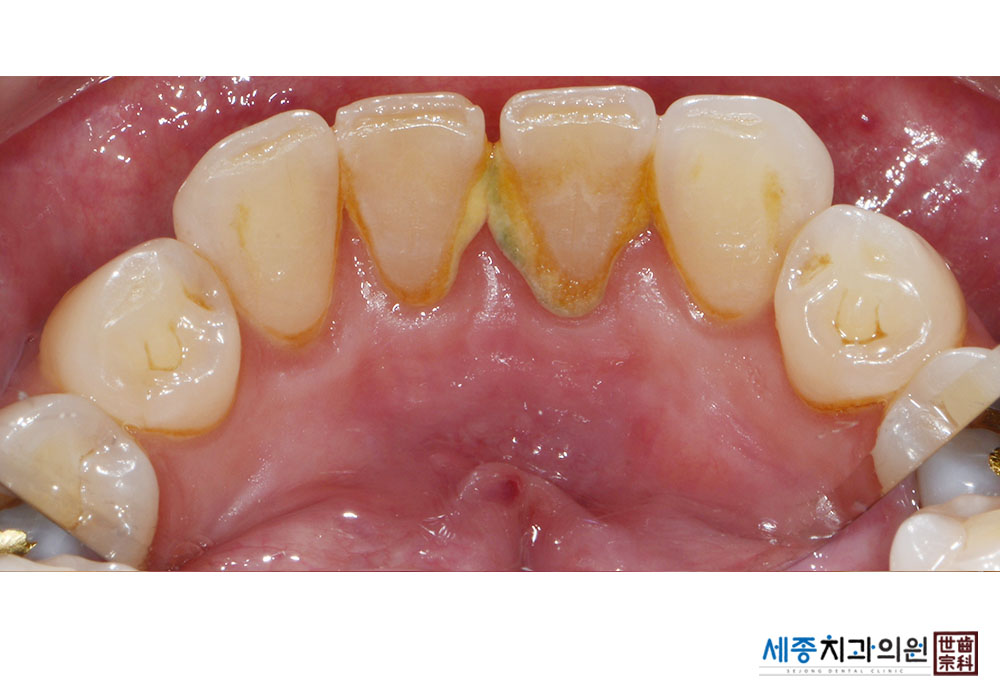

[스케일링] 치주질환 예방 스케일링

치료전 : 2020-06-25

치료후 : 2020-06-25

가글마취&저주파 스켈러를 사용한 스케일링